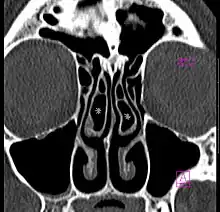

Concha bullosa bilatérale en scanner (coupe coronale)

La concha bullosa désigne la pneumatisation du cornet nasal moyen[1].

Il s'agit d'une variante anatomique fréquente, retrouvée chez près de la moitié de la population[2]. Elle est bilatérale dans la moitié des cas[2].